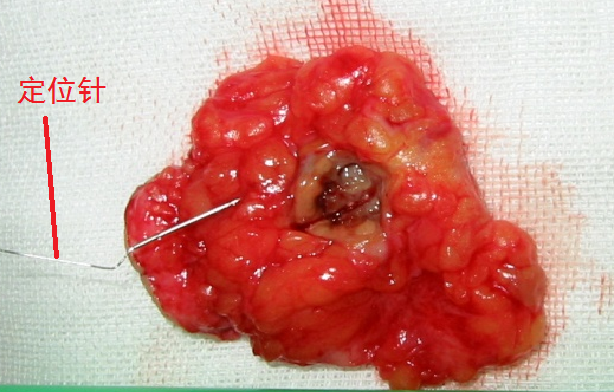

上图就是我们的乳腺定位针,针前方有倒钩。定位过程中,我们将定位针刺入结节内,穿刺到位后撤除针鞘,导丝前端的倒钩会自动弹开,这样定位针就能很稳固地固定在结节内部,不会滑脱。

手术切除乳腺小结节

我们从2007年开展不可触及乳腺结节定位针活检技术以来,已切除许多例B超或钼靶发现的乳腺小结节,部分乳腺小结节的术后病理回报为乳腺癌,我们应用该技术发现最小的早期乳腺癌病灶为3mm,患者免除了化疗痛苦。乳腺结节定位针技术真正践行了精准医疗理念,推动了乳腺癌早期发现、早期诊断、早期治疗,提高了患者生活质量。